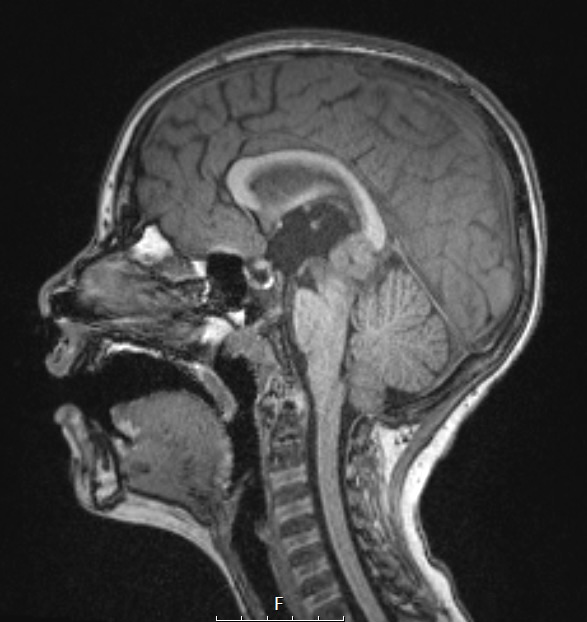

Case 18 History ---- The patient is a 9-year-old boy presenting with bilateral papilledema and symptomatic hydrocephalus. Imaging shows a lobulated, heterogeneously enhancing and diffusion-restricting 2.3 cm mass centered in the tectum of midbrain and pineal region with associated mass effect and obstructive hydrocephalus. Operative procedure: Endoscopic third ventriculostomy and biopsy of pineal tumor. ---- 18A1,2 A pineal mass is shown in T1 weighted scans without (18A1) and with (18A2) contrast.